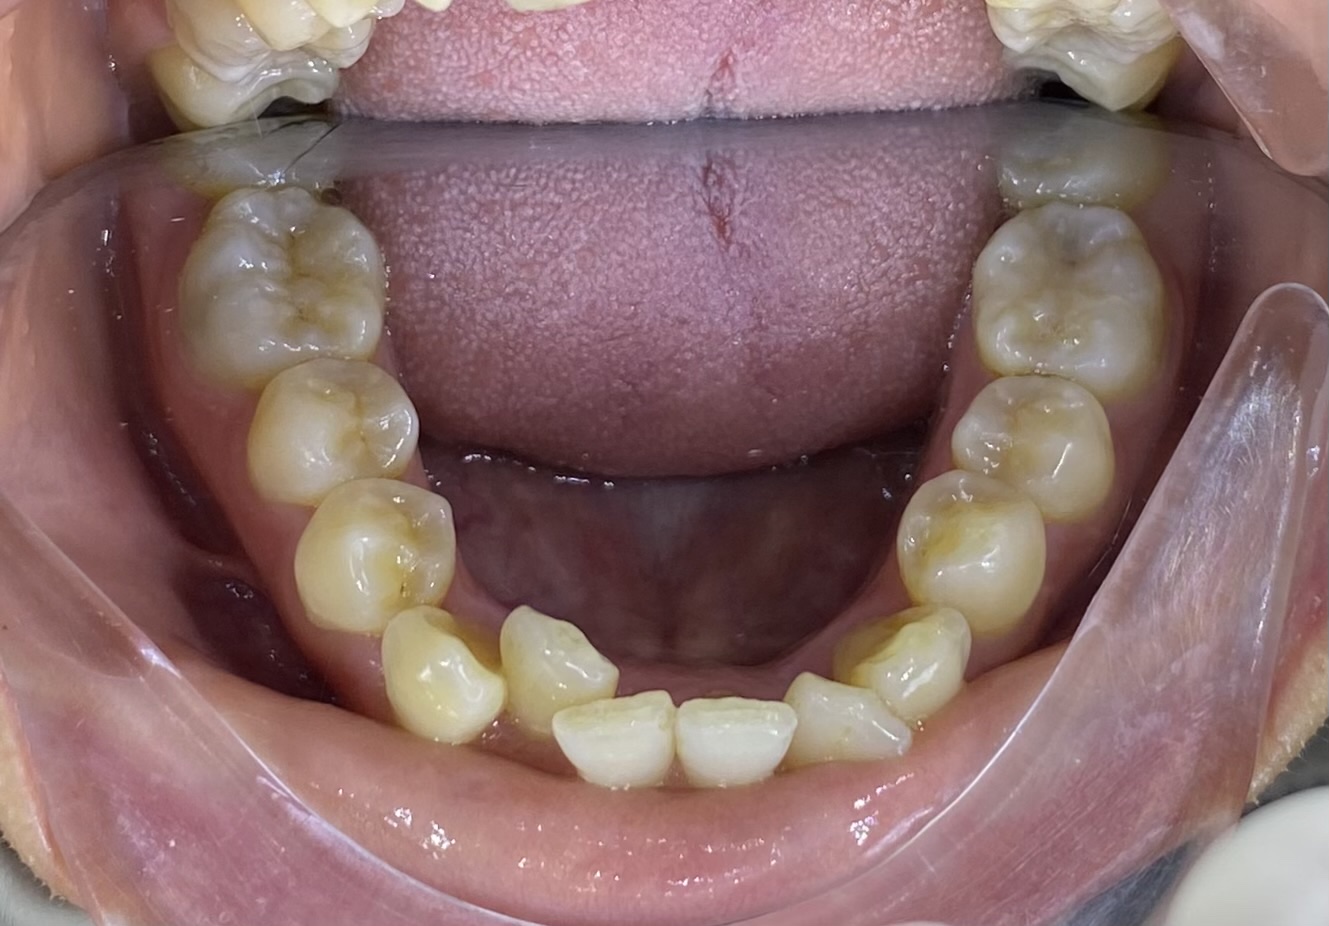

• Tình trạng răng ban đầu: Răng khấp khểnh, không đều,tình trạng hô nhẹ.

• Phương án thực hiện: Niềng hai hàm, có cắm minivis